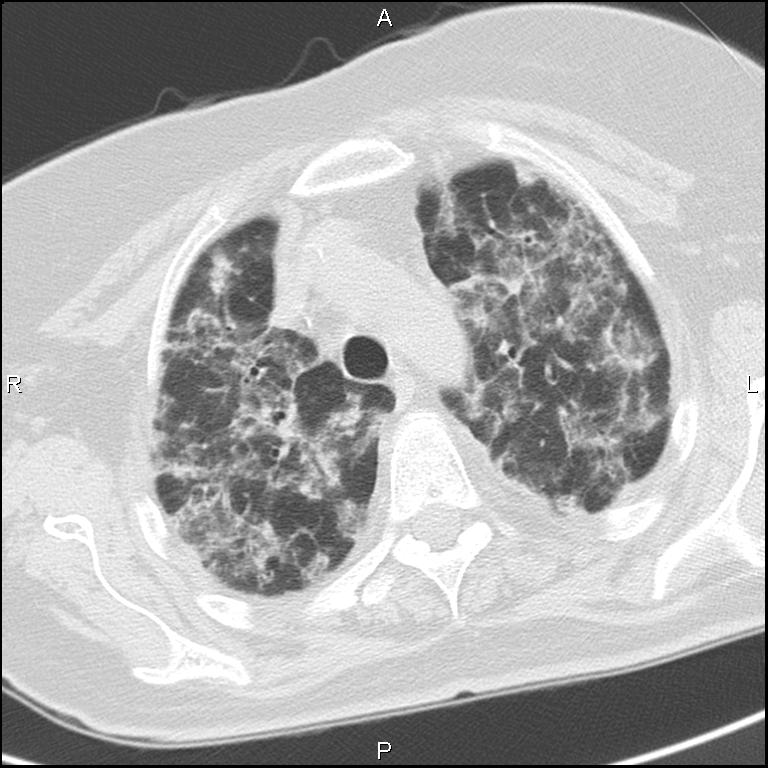

Визуализация и диагностика неинвазивного аспергиллеза с помощью КТ

Раздел: Необычные решения